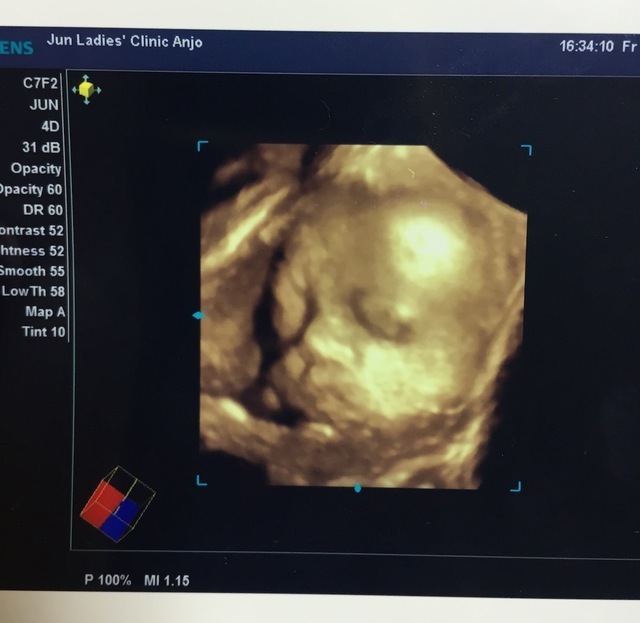

30週0日(30w0d・女の子)|moya さん(26歳)

エコー写真撮影時のエピソード:

実は今逆子ちゃんな我が子で、毎週逆子チェックしに行っています。いつも正しい位置に戻ってくれるか不安に思ってますが、久々に少しだけ顔が見れて元気そうな我が子を見たら、少しだけ不安が消えたような気がします。 逆子体操頑張ります!